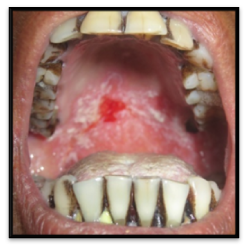

Figure 1 Shows the erythematous region in the palate.

The lesions were scrapable and left diffuse erythematous areas and bleeds on scraping. Smear made from scrapings of lesions were sent for cytological examination which confirmed the presence of candidal hyphae (Figure 3).

Figure 3 Photomicrograph demonstrates tubular-appearing fungal hyphae and ovoid yeasts of Candida albicans(Periodic acid–schiff stain).